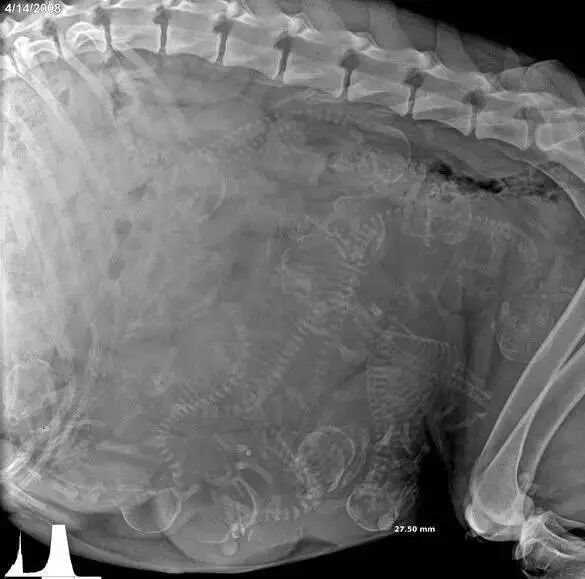

怀孕的豚鼠

还是豚鼠